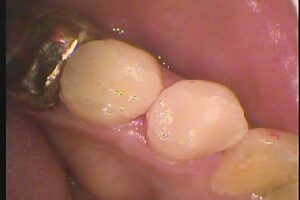

二本ともセラミックインレーにて修復しました。審美的だけでなく、セラミックは表面性状がツルツルしており、かぶせ、詰め物と歯との間に二次的虫歯が出来にくいといった点でも有利な材料となります。